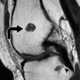

Multiple enchondromas

An enchondroma is a benign cartilage tumour found inside bones. Typically, enchondroma is discovered on an X-ray scan. [Source: Wikipedia ]